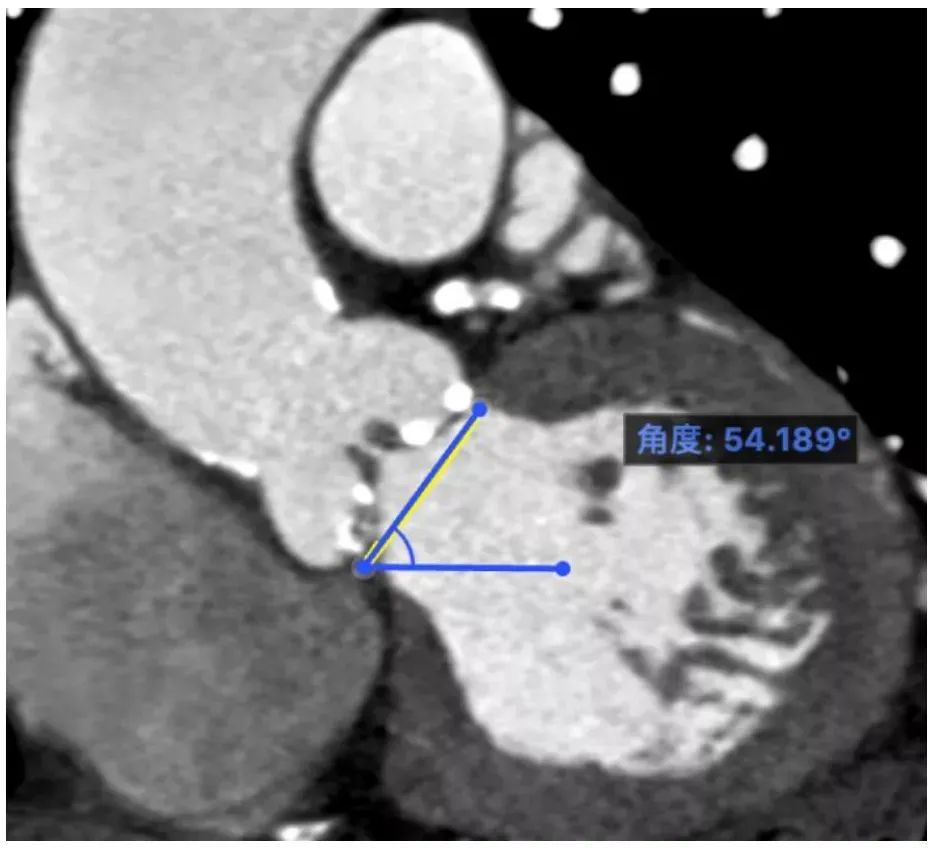

瓣环成角:54°

本例患者为三叶瓣重度钙化,同时合并冠脉疾病与二尖瓣狭窄。患者冠脉开口高度可,瓣环成角54°呈轻度横位心,腹主动脉段有附壁血栓,需缓慢输送大鞘,其他未见明显异常情况。经北医三院心内科唐熠达教授团队与多学科团队讨论后,决定同期行TAVR+PBMV+PCI手术,先处理冠脉病变再处理二尖瓣狭窄,最后处理主动脉瓣钙化。